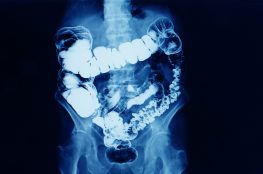

Kidney stones are hard deposits that form in the kidneys when there is an accumulation of minerals and salts in the urine. These deposits can range in size from a grain of sand to larger, more obstructive structures.

Bladder stones are mineralized formations that develop in the bladder when minerals in urine crystallize and clump together.